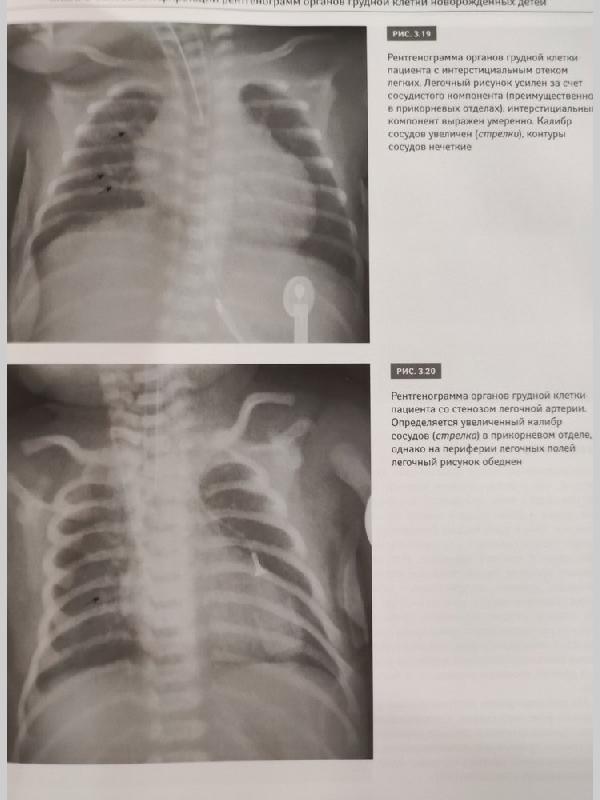

Рентгенодиагностика заболеваний легких у новорожденных детей: монография / М.В. Дегтярева, А.В. Горбунов, А.П. Мазаев, А.В. Ерохина. - М.: Логосфера, 2017. - 200 с. ISBN 978-5-98657-059-4 В монографии изложены основные подходы к рентгенодиагностике заболеваний легких у новорожденных детей, представлены развитие и нормальная анатомия легких, методика рентгенологического исследования, разобраны особенности интерпретации рентгеновских изображений грудной клетки и рентгеносемиотика заболеваний легких у самых маленьких пациентов. Книга содержит более 200 иллюстраций - рисунков и рентгенограмм органов грудной клетки и брюшной полости. Описаны сложные случаи диагностики и дифференциальной диагностики как редких пороков развития, так и часто встречающихся патологических состояний дыхательной системы новорожденных детей. Книга дополнена DVD с файлами рентгенограмм (цифровых и аналоговых), приведенных в книге. Данное издание предназначено для рентгенологов, неонатологов, педиатров, анестезиологов-реаниматологов, врачей скорой помощи, студентов медицинских вузов и других специалистов, работающих в смежных областях.